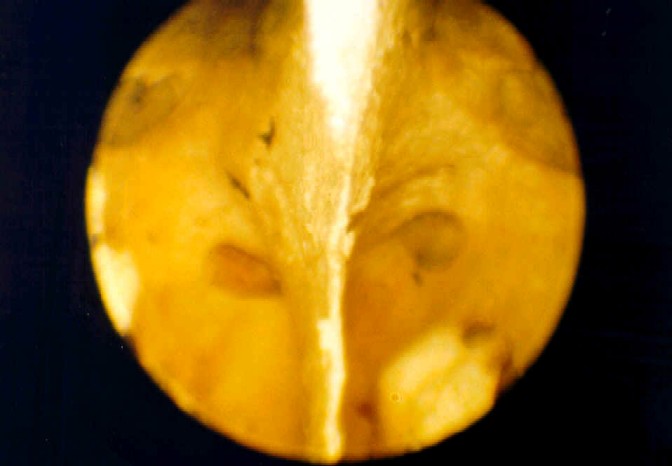

Cráneo óseo, transiluminación del seno esfenoidal. Se aprecian con

mayor brillo las áreas más delgadas de la pared lateral, correspondientes

a las estructuras vasculonerviosas. |